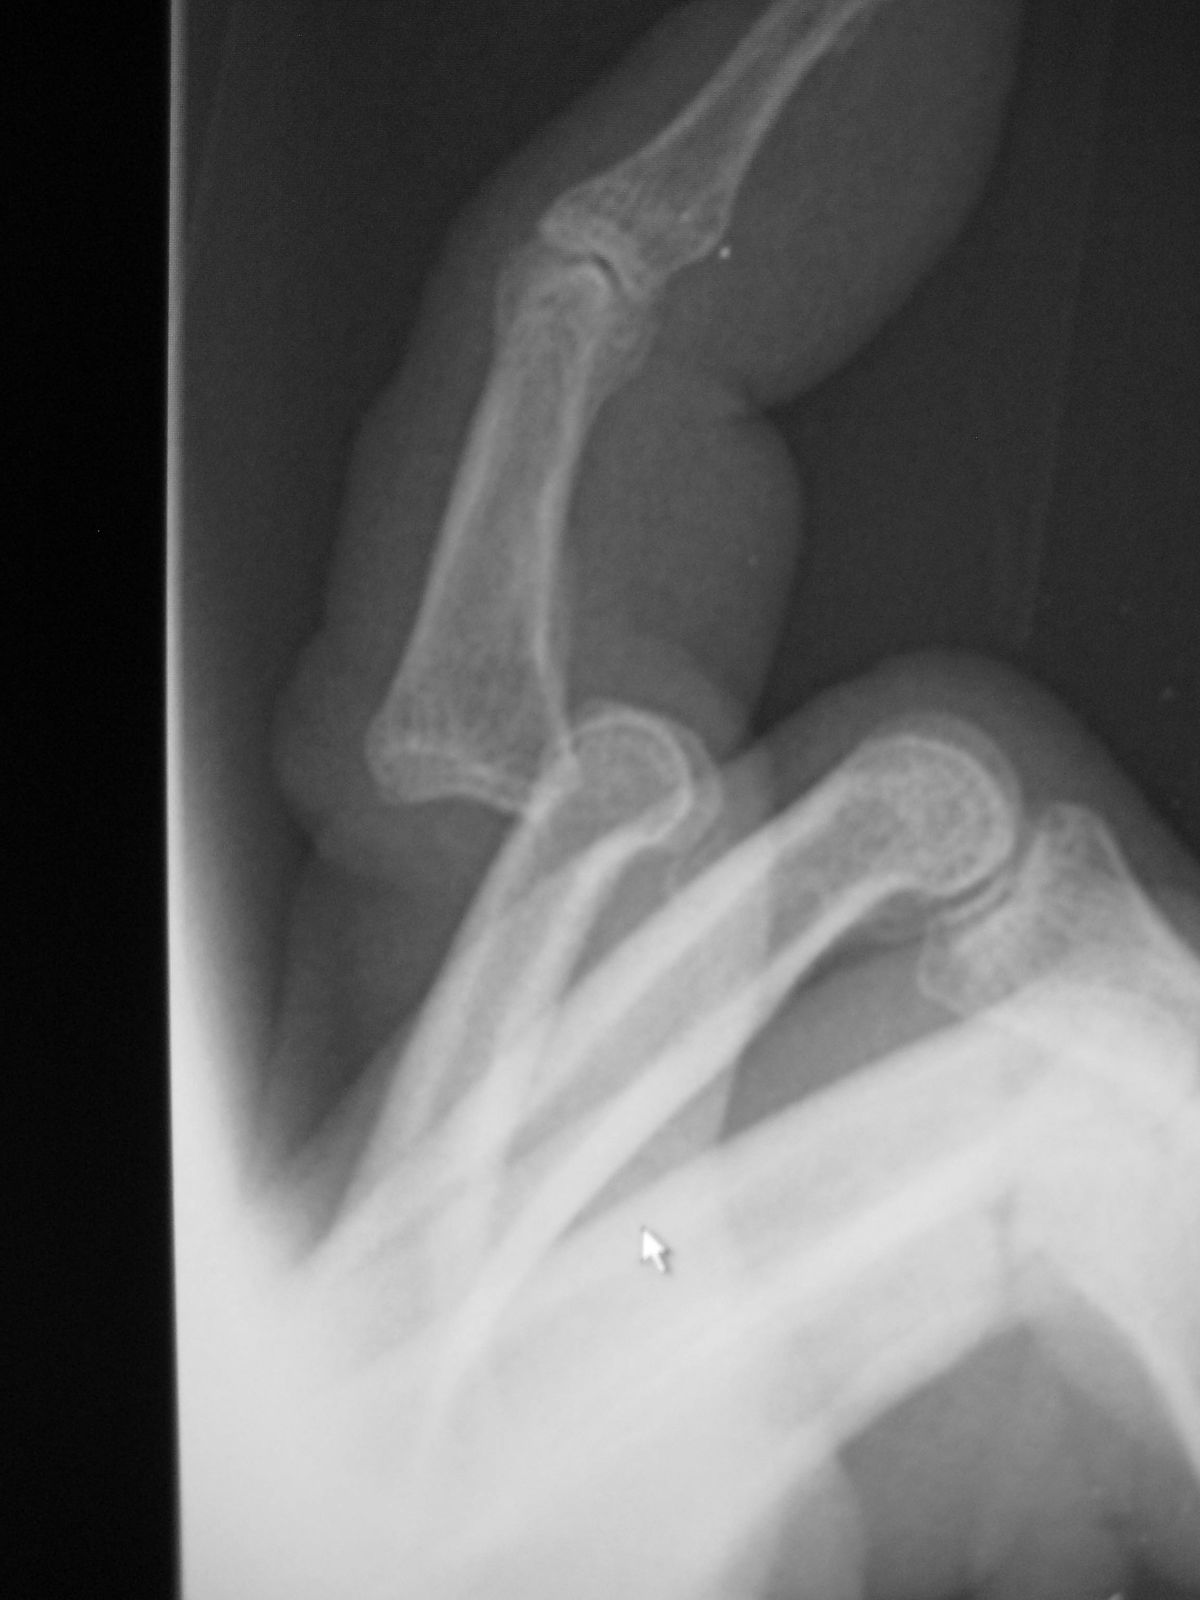

ねんざ:つき指

ねんざ